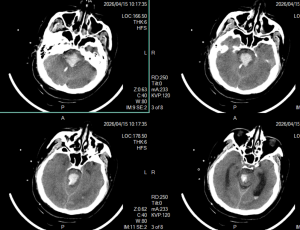

2026年4月29日 Home立体定向技术脑干出血急诊穿刺引流,抢救生命 脑干出血急诊穿刺引流,抢救生命 By admin 立体定向技术 0 Comments 病人1,4月13日急性脑干出血,迅速神志不清 术前CT显示脑干出血 脑干出血发病时 手术计划 术后复查,显示定位准确,穿刺道完全符合术前计划 术后7天,血肿基本引流干净 手术后15天情况 现病人生命体征平稳,正在促醒康复中 About Author admin Add a Comment 取消回复您的邮箱地址不会被公开。 必填项已用 * 标注Comment:*Name:* Email Address:* Website: Save my name, email, and website in this browser for the next time I comment. Δ